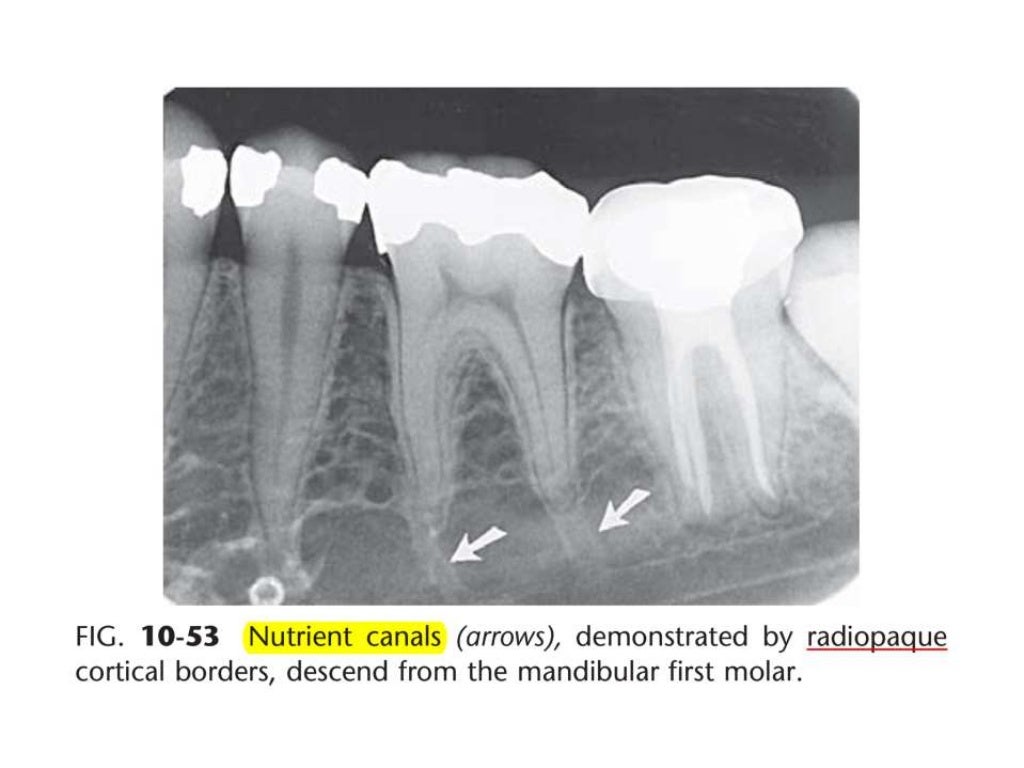

Intraoral Radiographic Anatomy Quizlet study with quizlet and memorize flashcards containing terms like radiolucent, radiopaque, what percent of enamel is mineralized?. Terms in this set (193) study with quizlet and memorize flashcards containing terms like nasal septum, nasal. study with quizlet and memorize flashcards containing terms like radiolucent, radiopaque, maxillary anterior landmarks. study with quizlet and memorize flashcards containing terms like nasal septum, nasal fossa, nasal spine and more. there are four anatomical landmarks frequently identifiable: study with quizlet and memorize flashcards containing terms like what is the ada's standard for viewing and interpreting. radiographic images are especially useful in the diagnosis and treatment of dental caries, periodontal bone loss, periapical pathosis. learn about radiographic film from intraoral radiographic anatomy dental ce course & enrich your knowledge in oral healthcare. describe the standard for image orientation, arrangement and viewing of intraoral radiographic images. study with quizlet and memorize flashcards containing terms like radiolucent, radiopaque, what percent of enamel is mineralized?. study with quizlet and memorize flashcards containing terms like cervical burnout, root caries, mesial concavity and more. Lingual foramen, nutrient canals, mental ridge, and inferior border of the. This is an online quiz called intraoral radiographic anatomy. intraoral radiography is the most frequently used radiographic procedure in dental radiology. Discuss the typical anatomic structures that. For each question select the correct response;.

Intraoral radiographic anatomy Intraoral Radiographic Anatomy Quizlet radiographic images are especially useful in the diagnosis and treatment of dental caries, periodontal bone loss, periapical pathosis. intraoral radiographic anatomy — quiz information. Lingual foramen, nutrient canals, mental ridge, and inferior border of the. intraoral radiographic anatomy will focus on the anatomical structures that are recorded on intraoral radiographic images. study with quizlet and memorize. Intraoral Radiographic Anatomy Quizlet.

Intraoral Radiographic Anatomy Intraoral Radiographic Anatomy Quizlet For each question select the correct response;. this chapter will deal with the basic terms of intraoral radiographic anatomy and key features in identifying. Lingual foramen, nutrient canals, mental ridge, and inferior border of the. study with quizlet and memorize flashcards containing terms like radiolucent is: Identify the different sizes of radiographic receptors. study with quizlet and. Intraoral Radiographic Anatomy Quizlet.